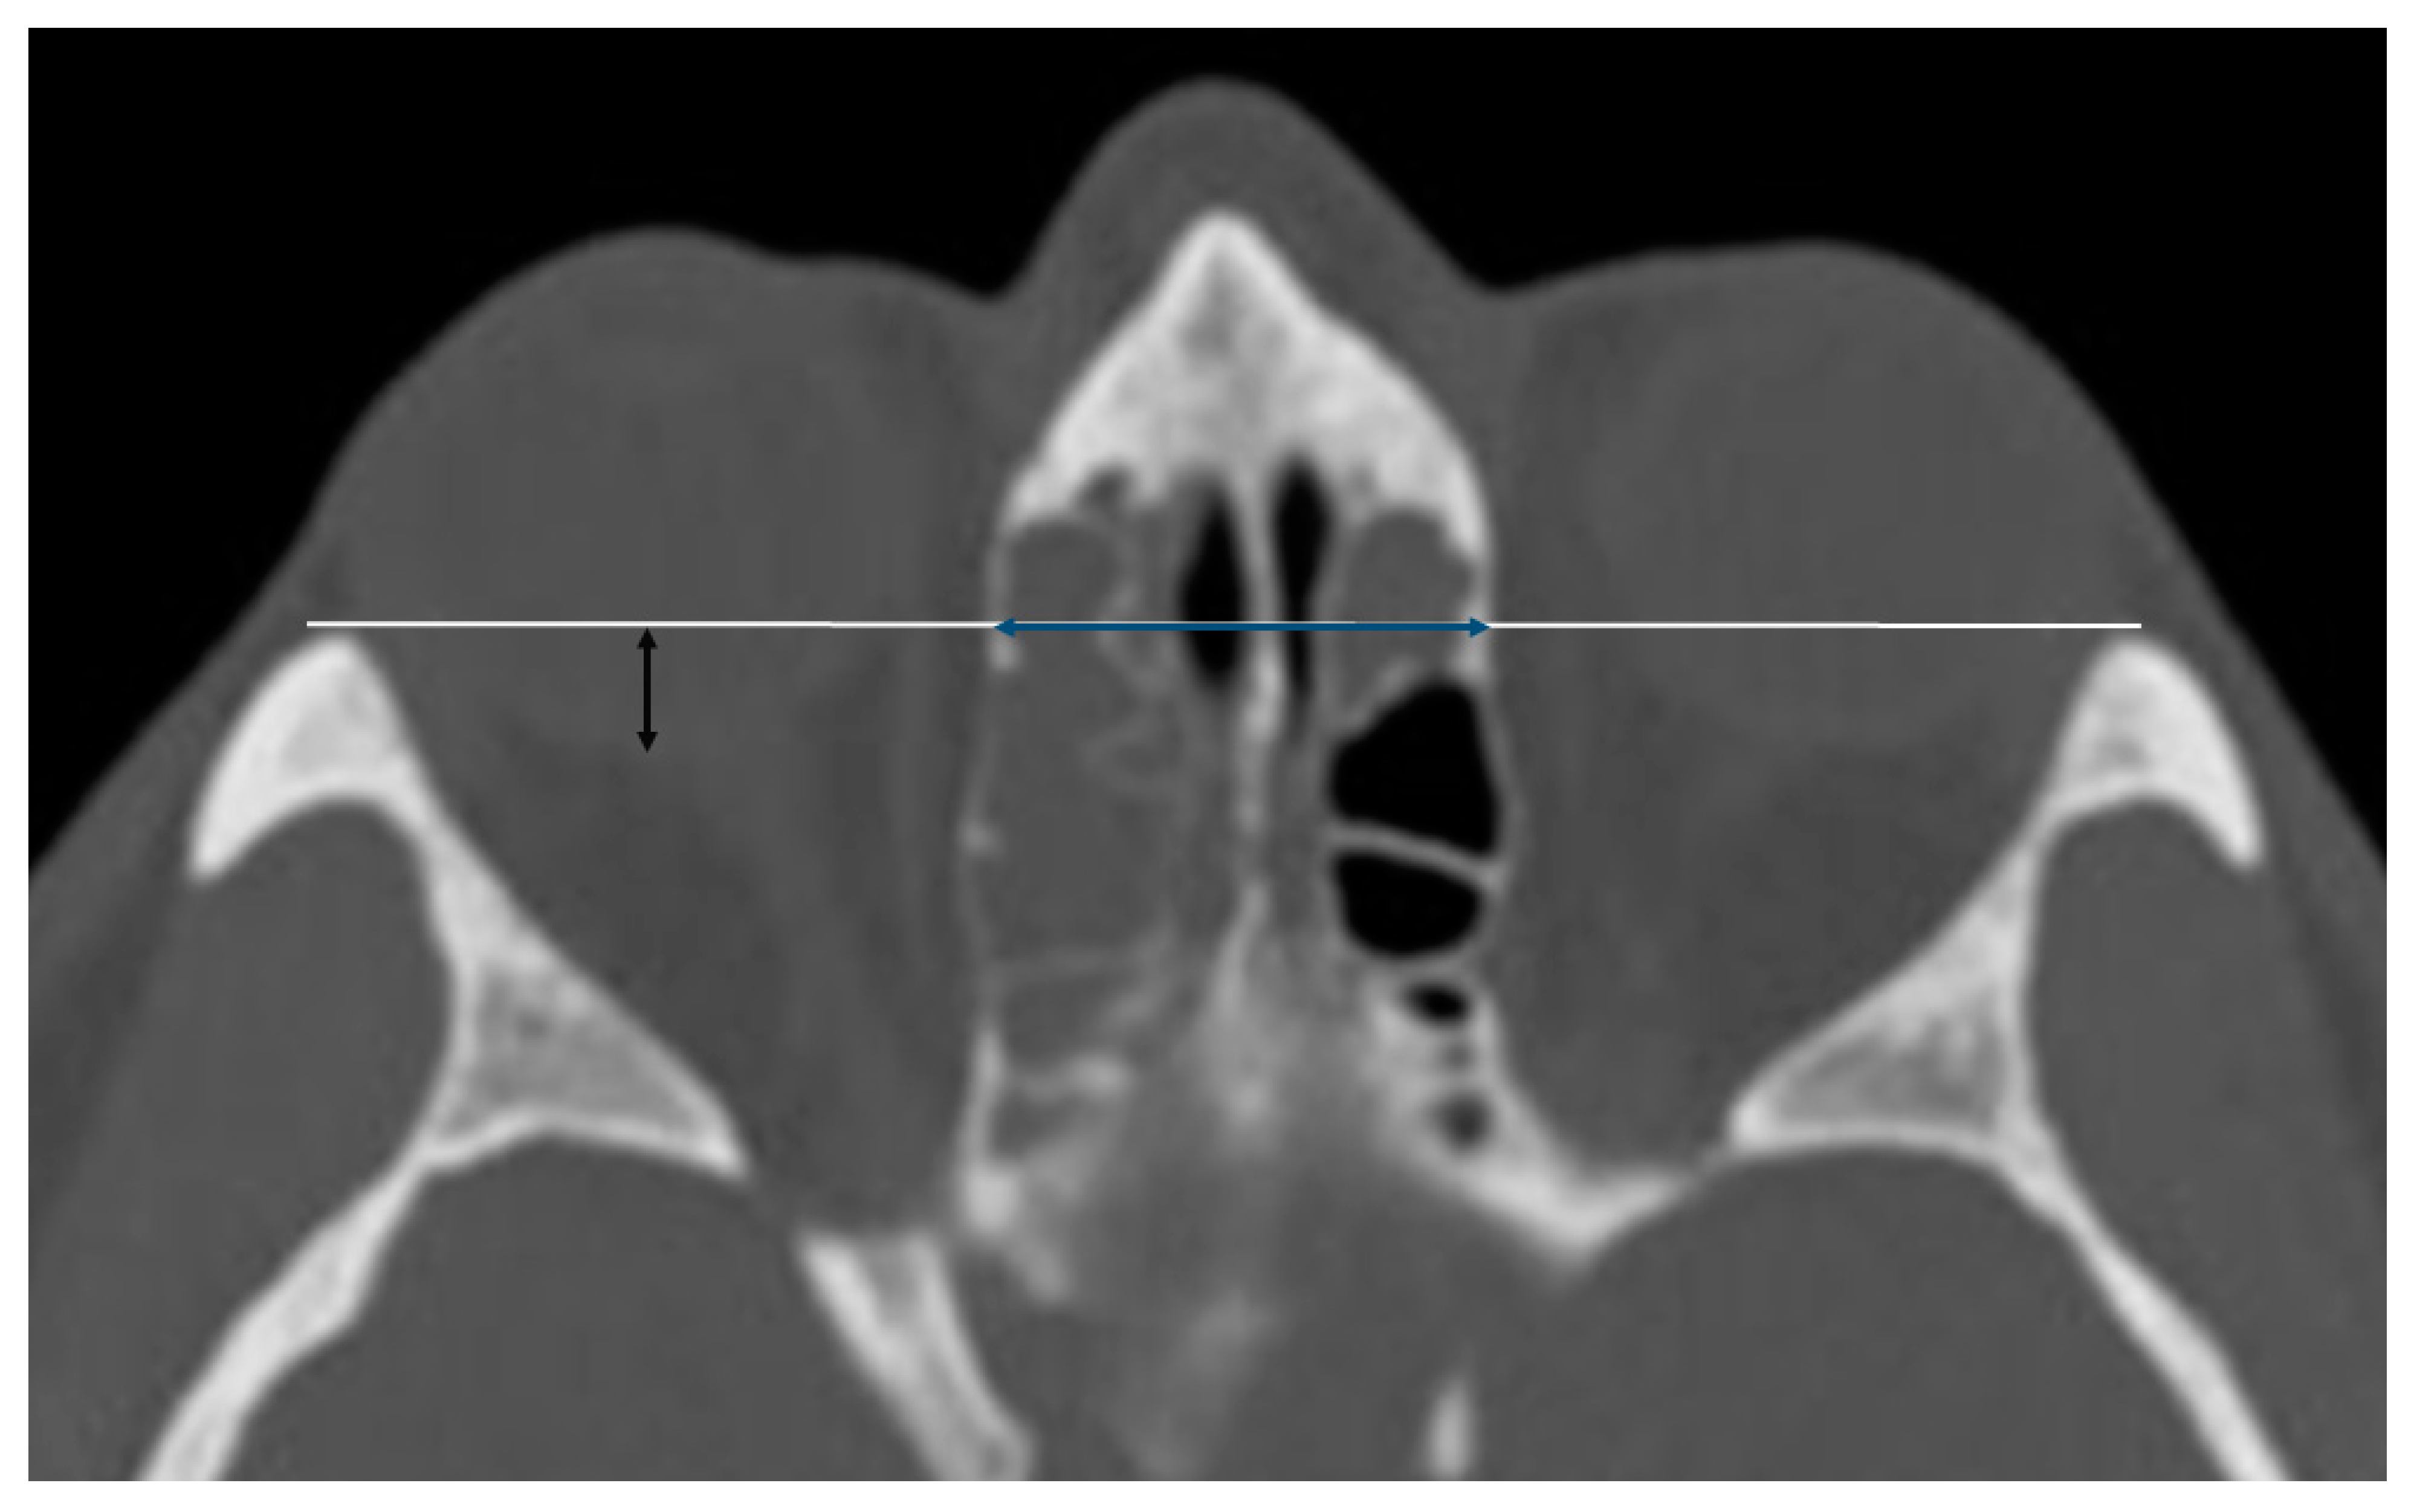

2.1.2. Globe Position

The antero-posterior position of the globe was measured in the axial plane on CT, using a horizontal line drawn from the medial tip of the lateral orbital rim to the contralateral orbital rim. The distance was measured from the horizontal line to the posterior edge of each globe passing through its midline (Figure 2).

In the axial plane, using a horizontal line drawn from the medial tip of the lateral orbital rim to the contralateral orbital rim, we measured the distance between the two laminae, which was defined as interorbital distance (IODaxial) (Figure 2).

Figure 2. Sinus computed tomography scan, axial plane. White line: horizontal line drawn from the medial tip of the lateral orbital rim to the contralateral orbital rim. Blue line: distance between the two laminae papyracea in the axial plane (IODAxial). Black line: represents the antero-posterior position of the right globe (PGP).